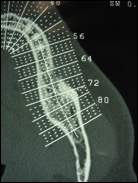

Il faut rechercher également les foyers infectieux et préciser la situation des sinus maxillaire et du nerf mandibulaire (qui traverse la mandibule) avant d’envisager la pose d’implants.

En cas d’obstacle anatomique (nerf trop proche, quantité d’os insuffisante…) une chirurgie pré-implantaire doit être programmée. Ainsi des greffes osseuses peuvent être envisagées avant la pose des implants, ou un déroutement des nerfs dentaires.